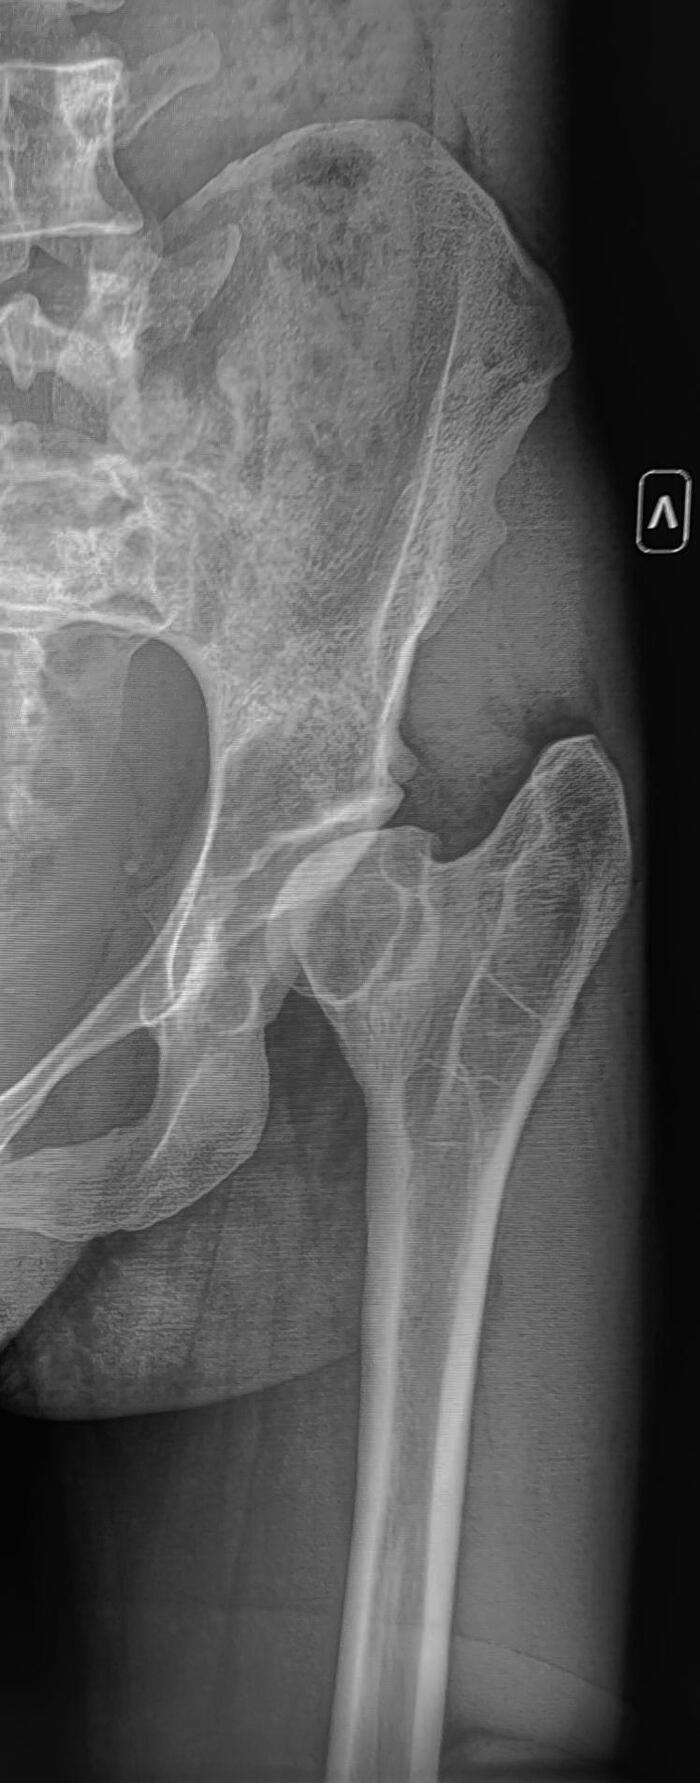

Рентгенография левого тазобедренного сустава молодого пациента с жалобы на боли ,ограничение движений в суставе.

Головка левой бедренной кости овоидно деформирована, уменьшена в размере, вертлужная впадина деформирована, уплощена, склерозирована, суставная щель неравномерно сужена. Шейка бедренной кости укорочена, расширена. Заключение: Признаки перенесенной болезни Пертеса левого тазобедренного сустава, вторичный коксартроз слева 2 ст.

Наиболее вероятно такая рентгенологическая картина сложилась вследствие не пролеченной болезни Пертеса в детском возрасте, что привело к деформации головки бедренной кости, вторичным изменениям в суставе.